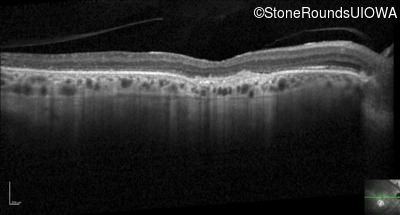

Optical Coherence Tomography - Left - 20/80

Exemplar / OCT Stack

Infrared Fundus Photograph - Right - 20/125 -2